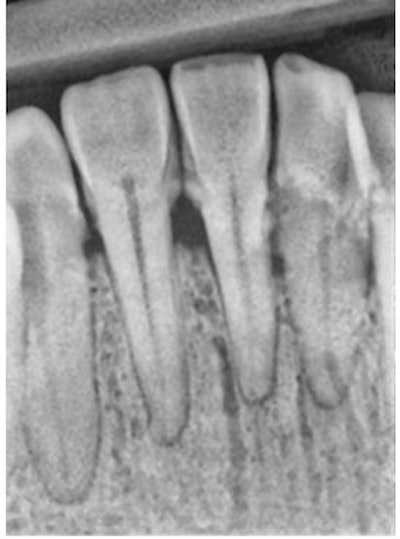

A similar type of evaluation can be done with periodontal disease using XDR software by Cyber Nedical Imaging.

On the left below is the initial radiograph, and on the right is the radiograph after enhancing the image.